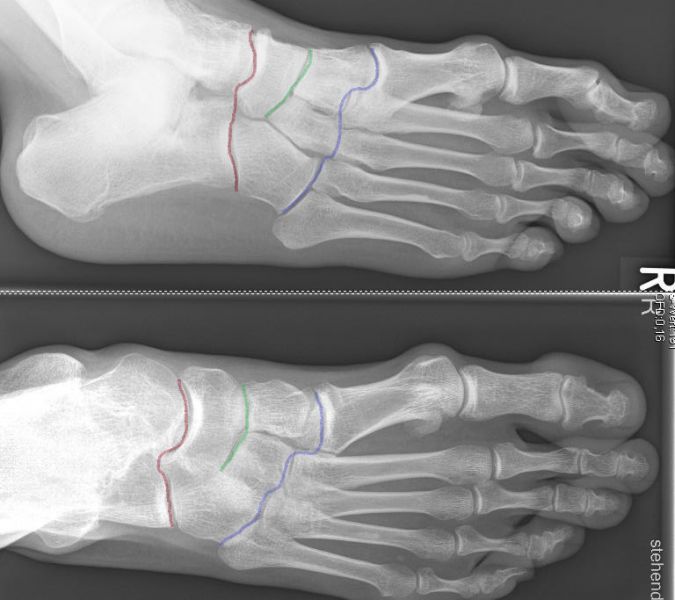

Unter den Mittelfußbereich fällt die Lisfranc- (blau), die Bona-Jäger- (grün) und Chopart- (rot) Gelenkreihe

Abbildung 1

Die Lisfranc-Gelenkreihe wird aus den Ossa cuneiformia/Os cuboideum und den jeweiligen Metatarsalia gebildet. Die Bona-Jäger-Gelenkreihe liegt zwischen dem Os naviculare und den Ossa cuneiformia. Die Chopart-Gelenkreihe wird aus Talus/Calcaneus und Os naviculare/Os cuboideum gebildet. Vor allem ist die Lisfranc-Gelenk-Linie von degenerativen Veränderungen betroffen, hierbei häufiger die mediale Säule, also die Tarsometatarsal-Gelenke I-III.